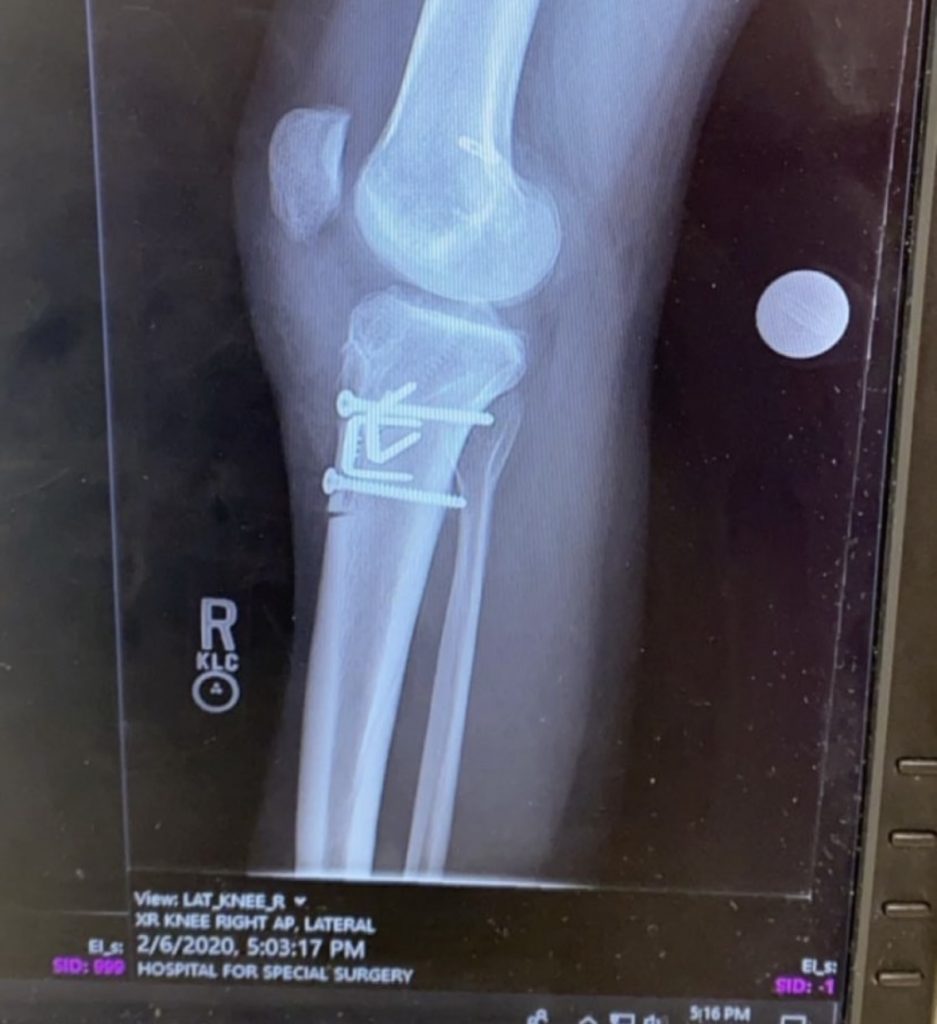

Dr. Strickland was my last hope for an injury that started back in 2015 and kept reoccurring despite surgical and physical therapy interventions. I had torn my right ACL twice and lived with constant instability and pain. Before my appointment, I had x-rays taken, and by the time I was seated in the examination room, Dr. Strickland already had an idea of what was occurring to me. Due to the issue's complexity, Dr. Strickland collaborated with Dr. Gomoll; I was born with a misshaped tibia, which was why I kept experiencing injury to my right ACL.

On December 23, 2019, I had my fourth knee surgery to correct the bone abnormality and, once again, my ACL. If it were not for this surgery and the following surgery to remove the hardware nine months later, I would never be able to accomplish half the things I have. One of my biggest fears about having this invasive procedure was not being able to continue my education in nursing school. Dr. Strickland and Dr. Gomoll reassured me and promised that this surgery would help me and not hold me back any more than my injuries already did. Today, I work in Emergency Medicine as a Registered Nurse, accomplishing things I never dreamed of for myself.